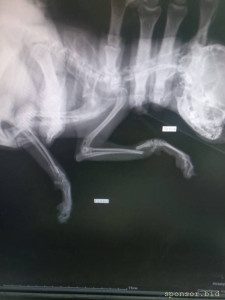

🆘🆘🆘 ПОМОГИТЕ ОПЛАТИТЬ ОПЕРАЦИЮ! Маленький той , сломала две передних лапки. Лапки просто отломленный, болтаются. Срочно нужно прооперировать🤧Стоимость такой операции 28.000 тыс рублей, одна лапка 12-14 тыс ((((( Друзья, помогите поставить девочку на лапки 🙏🏻🙏🏻🙏🏻

Помогите сохранить лапки тойчику 128591; - 20230419_204628.jpg